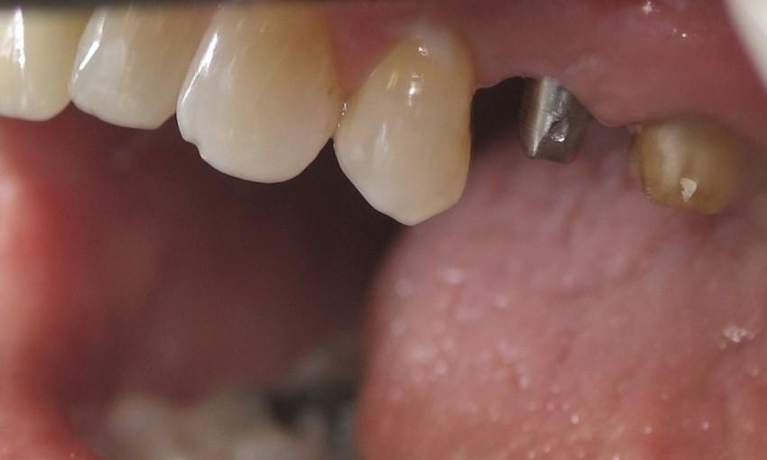

Are you considering dentistry at Michael J Nelson DDS? If so, we’d like to invite you to browse our Smile Gallery. Our dental team can improve your oral health and help you attain the attractive smile you’ve always wanted.